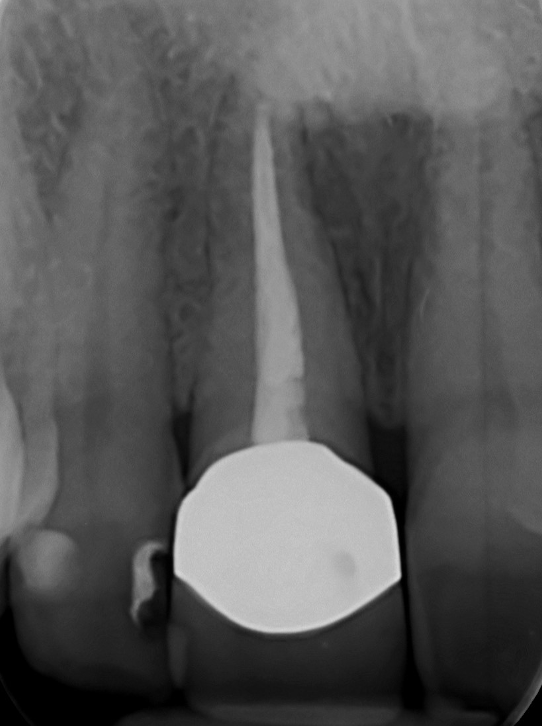

The main issue involved the upper right central incisor (tooth 1.1), which was devitalized and presented recurrent abscesses. Clinical and radiographic evaluation confirmed the presence of buccal bone wall resorption, leading to a significant defect in the alveolar ridge. This condition compromised both the hard tissue and the surrounding soft tissue, posing a challenge for achieving long-term stability and esthetic success in the anterior maxilla.

The surgical protocol began with the atraumatic extraction of tooth 1.1 to preserve as much of the alveolar socket as possible. Immediately following extraction, an N1 implant was placed into the socket using a guided surgical approach to ensure ideal three-dimensional positioning. The “one abutment one time” technique was applied to minimize soft tissue manipulation during the healing phase, which is particularly important in esthetic areas.

On the same day as the surgery, an immediate-load provisional crown was delivered. This restoration was fabricated in acrylic resin and screw-retained on the implant, following the “one abutment one time” principle. The provisional crown was carefully adjusted to avoid occlusal loading while supporting the peri-implant soft tissue architecture during the healing phase.